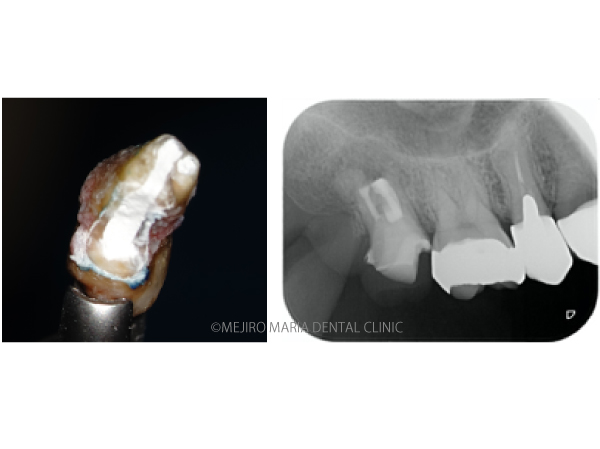

右上の奥歯付近に“できもの”ができたことを主訴に来院された患者様の症例です。当院での診査の結果、右上7番の根尖性歯周炎と診断しました。しかし、一部に限局的に進行している歯周ポケットが確認できたため、歯根破折もしくは歯内歯周病変が疑われました。患者様は診断的な意味合い(歯根破折の確認)も含め、被せものを外して精密根管治療を開始することを希望されました。

精密根管治療の開始後、根管内充填物(感染物)を除去して根管内を確認すると、歯根破折が見られました(中央写真の赤矢印)。歯根破折は根管内に留まっていましたが、歯周ポケットと繋がっていたため、1回目の治療を中止しました。

歯牙を抜歯後、メチレンブルーにて染色して破折線を確認しました。破折線に沿って感染部位を除去しましたが、根管内部の構造が非常に複雑なため、最終的な形態は、真ん中の写真のようにしました。